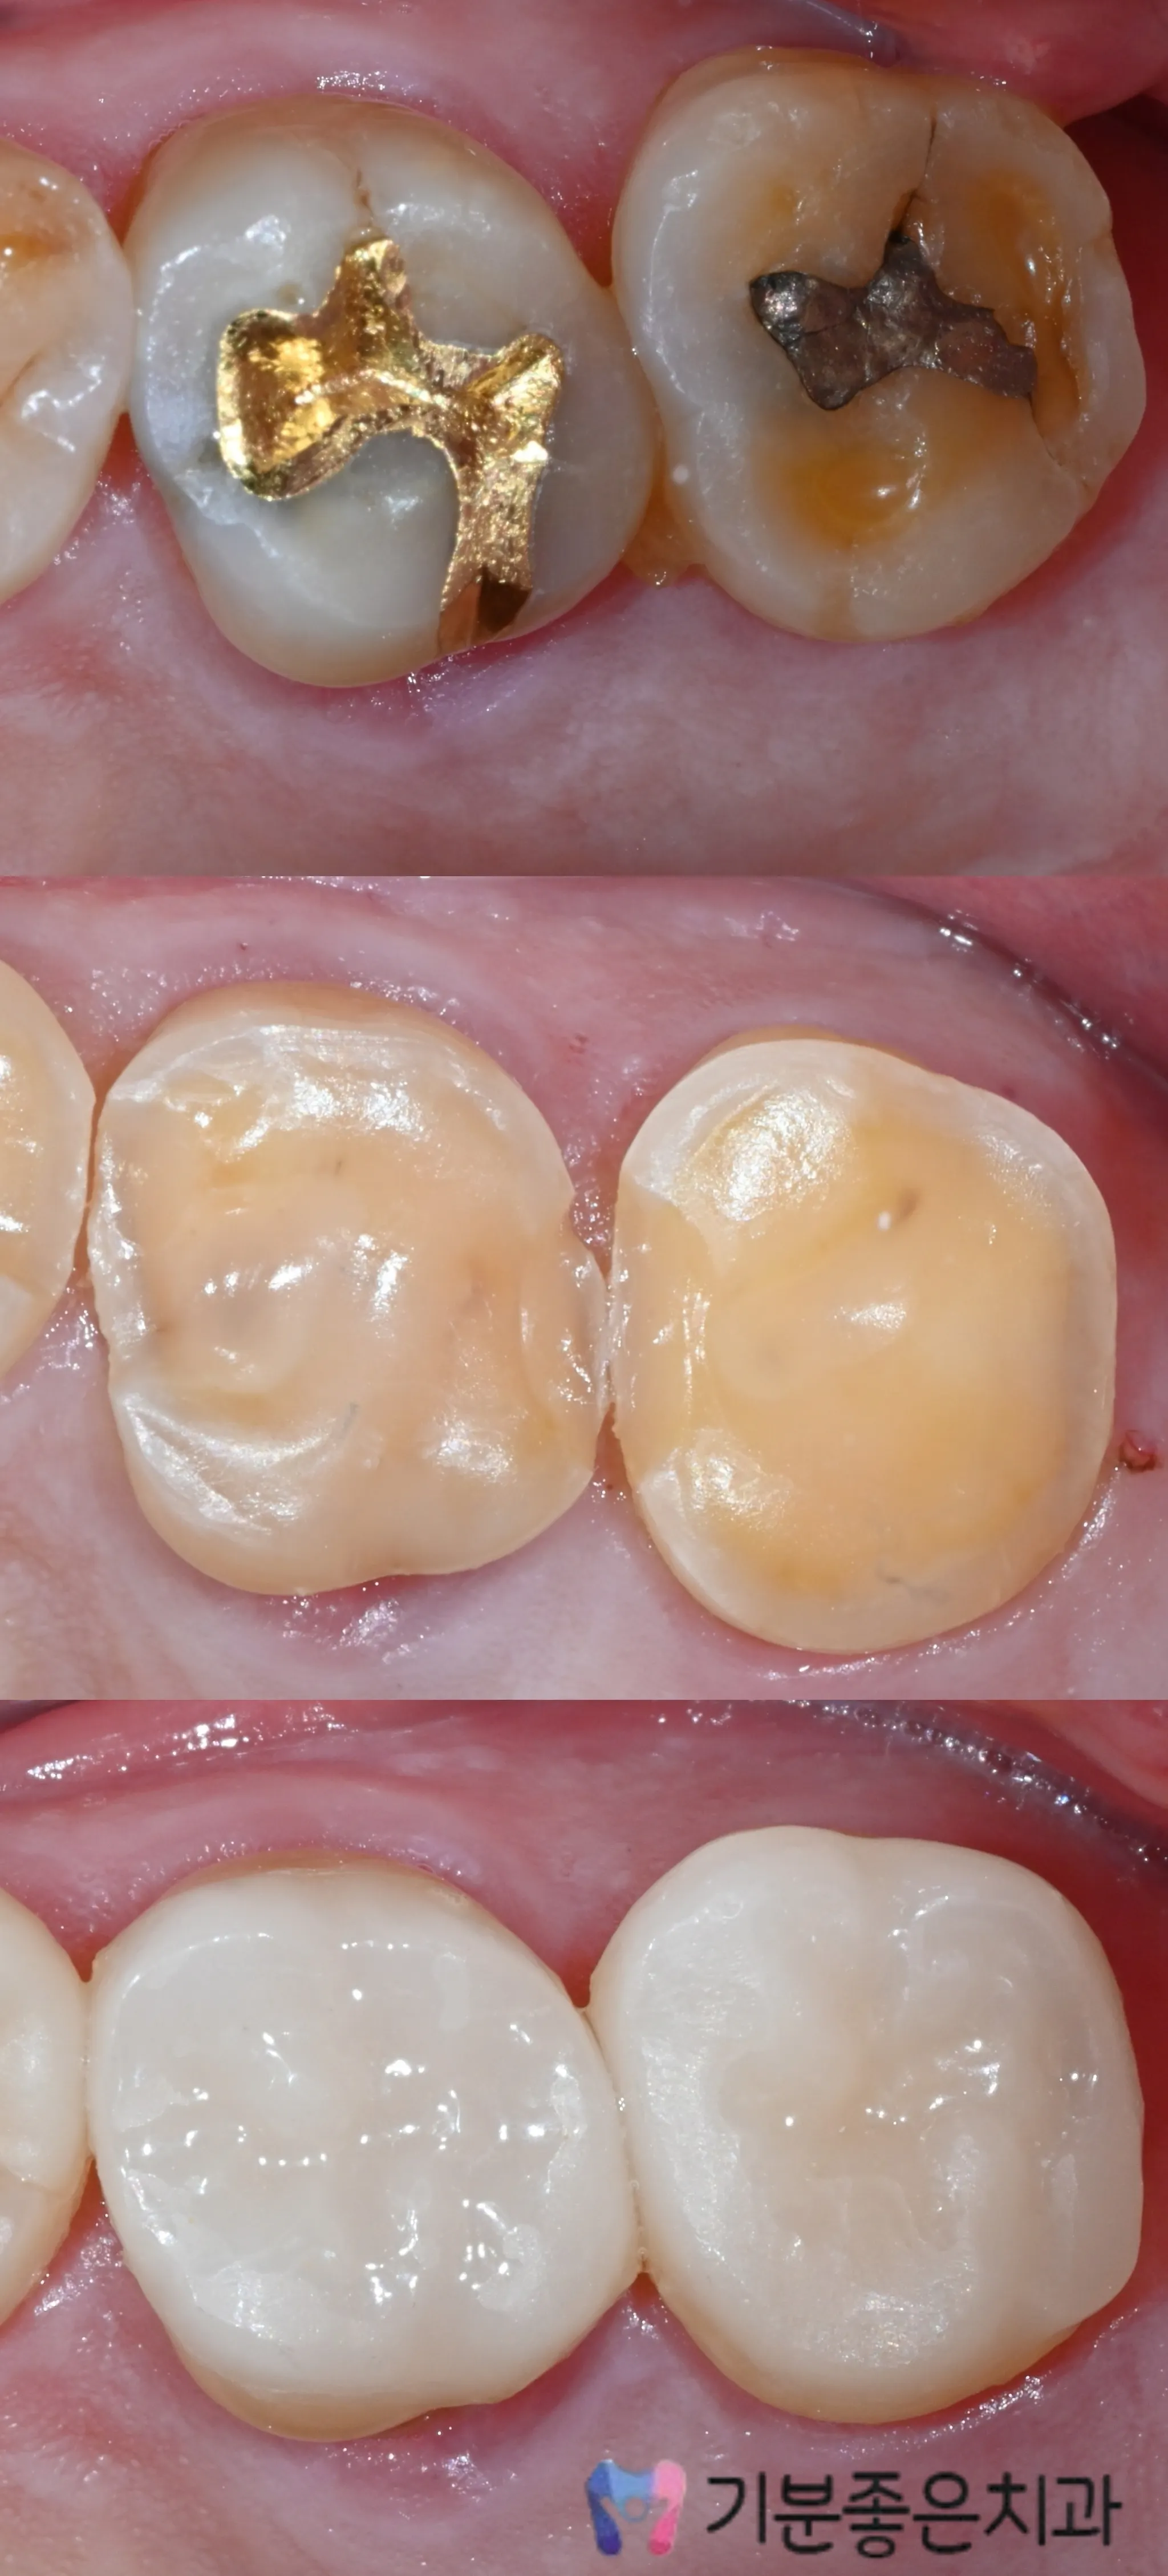

02 - Overlay

An overlay is a modern restorative treatment that protects the damaged portion of a tooth without extensively reducing the entire tooth structure like a full crown.

Overlays rely on advanced adhesive bonding rather than mechanical retention, making precise bonding technique essential for long-term success.

Performed using a standardized, controlled procedure to ensure durability and predictable prognosis. At Feel Good Dental, overlays are not treated as simply โless-prep crowns,โ but as precision-driven restorative procedures designed for long-term stability.

* Overlays may not be suitable depending on the extent of tooth cracks, remaining tooth structure, or occlusion (biting force). After diagnosis, we will guide you toward the safest method.